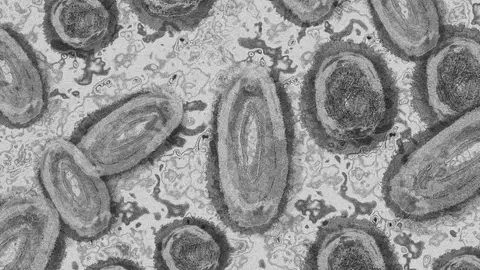

MPOX

La viruela del mono es una enfermedad rara causada por la infección con el virus del Mpox. Este virus, aunque pertenece a la misma familia del virus de la viruela, es menos contagioso que ella y tiene síntomas más leves. En general, no es mortal.